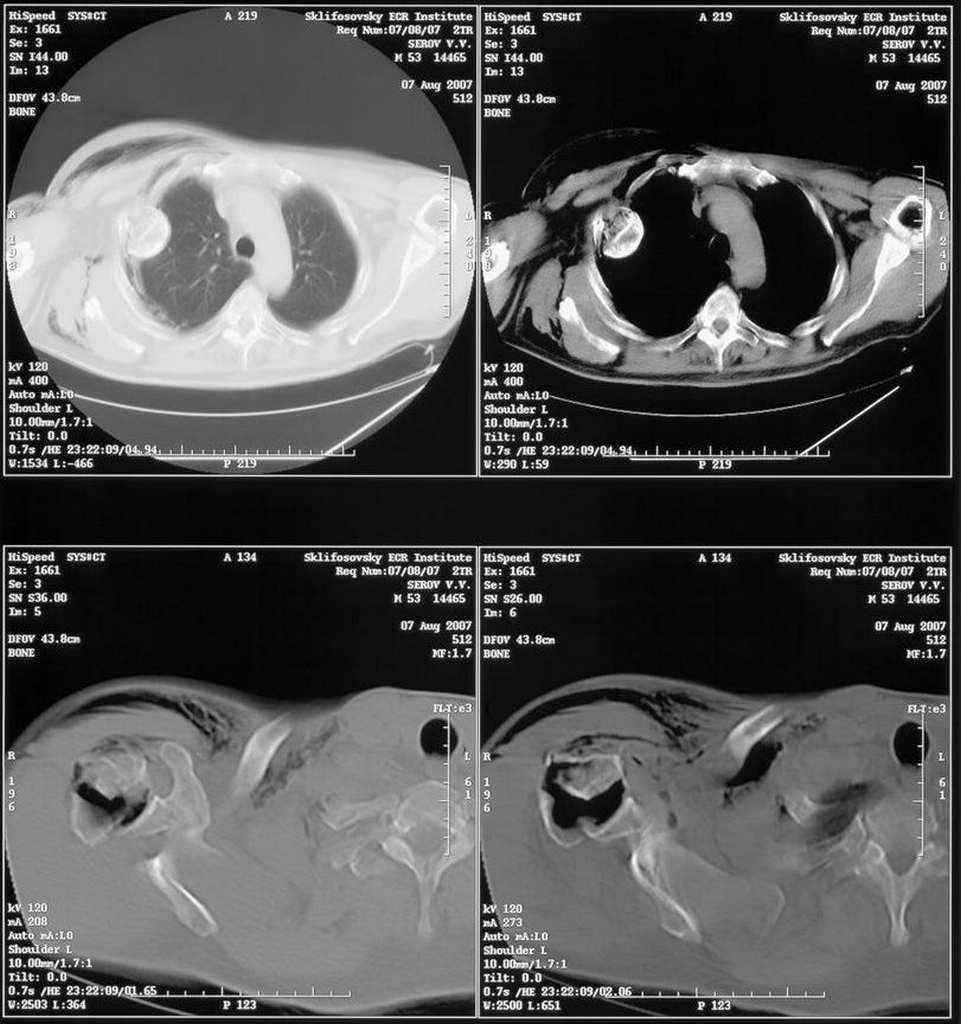

Правый плечевой сустав умеренно деформирован. По внутренней поверхности  плеча имеется кровоподтек. При пальпации плечевого сустава имеется умеренная болезненность. Активные и пассивные движения болезненные. Снижена чувствительность по тыльной поверхности пальцев кисти и отсутствует активное разгибание кисти и пальцев. Имеется подкожная эмфизема шеи, верхней половины грудной клетки (рис 1, 2). На рентгенограмме: оскольчатый перелом головки плечевой кости со значительным смещением, перелом 2-3 ребер справа, тканевая эмфизема (рис 3). КТ при поступлении: перелом головки плечевой кости в области анатомической шейки со смещением отломка головки в грудную полость, правосторонний гидроторакс, перелом 2-3-4 ребер справа. (рис 4). Через двое суток после поступления выполнена операция: атипичная торакотомия, эвакуация свернувшегося гемоторакса, удаление инородного тела (головки плечевой кости) из плевральной полости (при этом выявлено имеющееся повреждение париетального и висцерального листков плевры) (рис. 5), дренирование плевральной полости, замещение проксимального конца плечевой кости спейсером из костного цемента с антибиотиком (рис. 6). Послеоперационный период протекал гладко. При контрольной рентгенографии положение спейсера удовлетворительное (рис. 7, 8). Дренаж из плевральной полости удален через 3 суток после вмешательства. Послеоперационная рана зажила первичным натяжением. Через 12 дней после операции больной выписан на амбулаторное лечение.